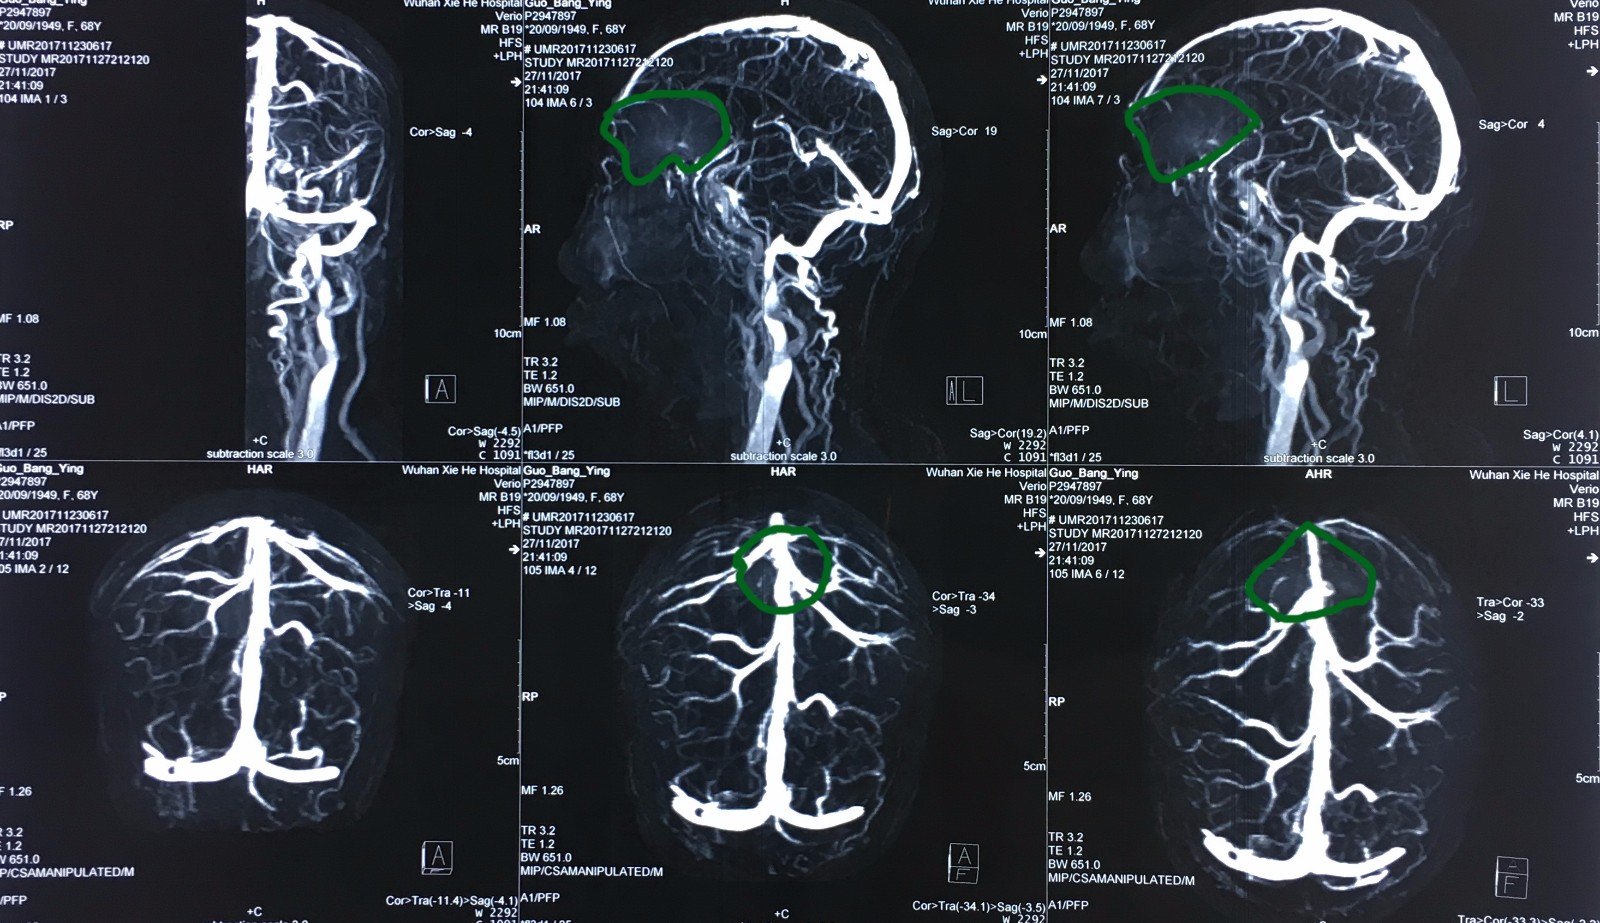

术前的核磁共振动脉造影,显示大脑前动脉及其分支被肿瘤向后及上方

图片尺寸1600x923